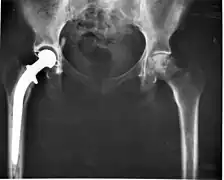

- (anatomy) The rounded part of a bone fitting into a depression in another bone to form a ball-and-socket joint.

Head of the hip bone.